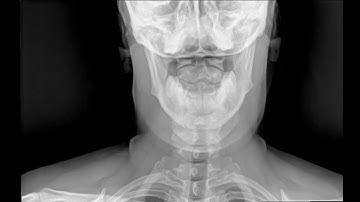

Dynamic Digital Radiology View of C Spine Fuchs Imaging